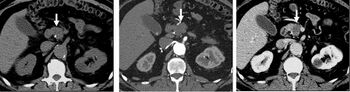

FIGURE 7. Selected images from a renal mass specific protocol CT. Corticomedullary phase (axial 7a) demonstrates peripheral enhancement of the renal cortex with minimal opacification of the renal medulla. There is a large renal cell carcinoma in the left kidney (right in image) which can be differentiated from the normal renal parenchyma by the heterogeneous and differential enhancement. The renal artery and vein are opacified in this phase as well. The collecting system is not opacified (coronal reformat 7b). In the parenchymal phase, the renal cortex and the medulla are enhancing. The renal cell carcinoma in the left kidney is not as well defined when compared to the corticomedullary phase images, but is actually slightly more conspicuous. There is some contrast noted within the collecting system during this phase (7c).[citation needed]